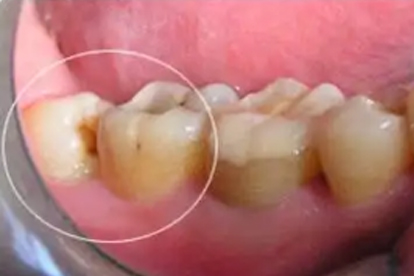

发生深度龋坏的智齿通常需要拔除。由于智齿位置靠后,清洁难度大,龋坏进展快且修复效果差。严重龋坏可能引发牙髓炎或根尖周炎,出现自发痛、咬合痛等症状。对于无法通过充填或根管治疗保留的智齿,拔除是更彻底的治疗方案。